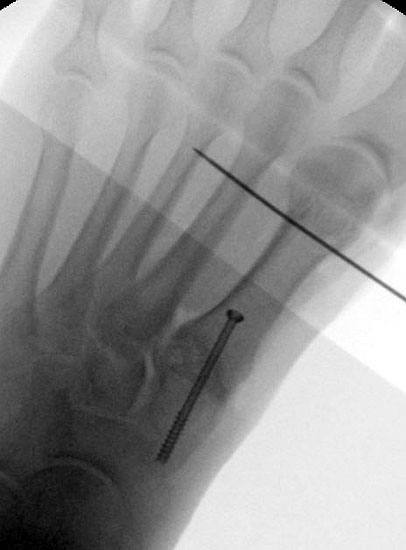

Röntgenaufnahme des Fußes im Stehen im dorsoplantaren und seitlichen Strahlengang (Abb. 1a-b).

Abbildung 1a

Abbildung 1b